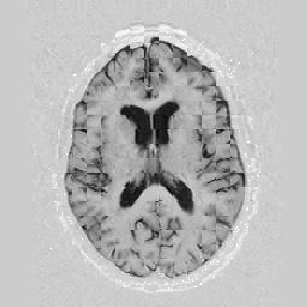

I later attempted 10 iterations at level 2, then 2 iterations at level 1, and 1 iteration at the finest level. Visual results can be seen in Figure [*].

Figure: Multi-scale NRR. From left to right, top then bottom: before NRR; after 10 iterations of NRR at level 2; after another 2 iterations of NRR at level 1; after 1 iteration at level 0.